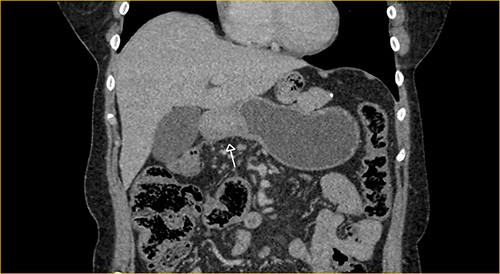

Laboratory examination showed anemia. An excluded stomach distention and parietal thickening of the pylorus and antrum were identified during abdominal computed tomography (CT) and magnetic resonance imaging (Figs 1–4). Thoracic CT was normal.

Coronal section on contrast magnetic resonance showing excluded stomach distention with parietal thickening of the pylorus and antrum (arrow).